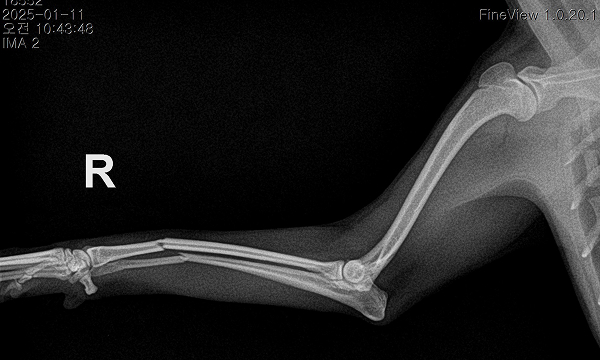

수술케이스 ② 보*강아지 - 요척골 단순골절

수술케이스 2 before BEFORE